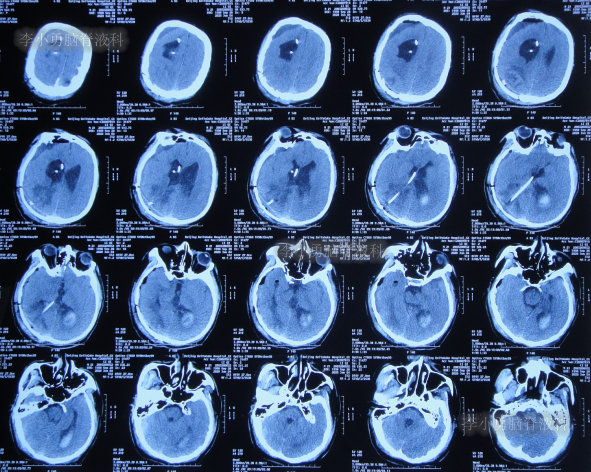

发现脑积水11年即2016年7月20日,复查头颅CT(图-2)后,仍建议继续定期观察。

图-2:2016年7月20日头颅CT